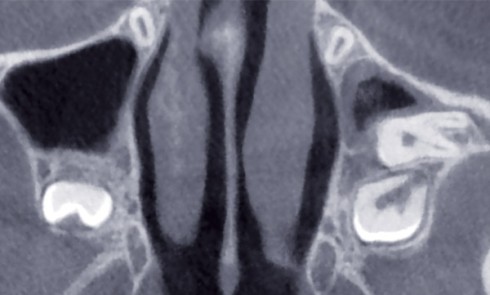

Article réservé à nos abonnés Démarche diagnostique clinique et radiologique face à une dent incluse

L’inclusion dentaire est définie comme une « dent retenue dans l’arcade maxillaire ou mandibulaire au-delà de la date d’éruption, entourée de...